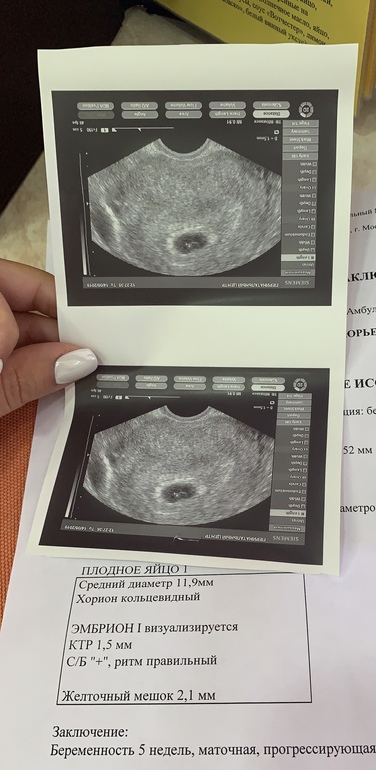

22дпп первое узи 😍

Я БЕРЕМЕННА !Наше первое узи , врачу все понравилось , а мне тем более , и эмбрион и сердечко, один мой птенчик , дай бог чтобы все было хорошо 🙏🏻🙏🏻🙏🏻🙏🏻🙏🏻